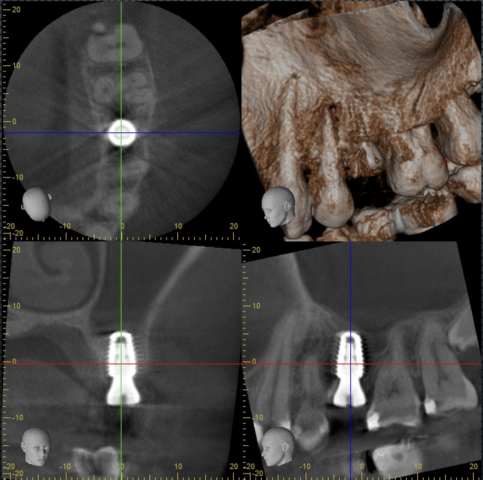

インプラント診査

抜歯後3ヶ月待ってインプラント治療を行いました。青色がインプラントシミュレーションとなります。上顎洞底までの距離が短いため注意が必要な症例です。

術後CT

インプラントを入れた直後のCTとなります。上顎洞底骨を若干底上げして埋入しています。術後の腫れや痛みは皆無でした。